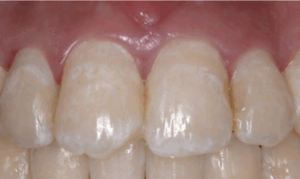

これが、虫歯の第一段階CO(シーオー)です。

歯医者で治療するまではないが要注意の歯になります。

お家では、フッ素の入った歯磨き粉で磨いていただくといったセルフケアが必要となります。

これを放っていると虫歯になってしまいます😖

自覚症状として、痛みは全くないが見た感じ少し白く濁っています。